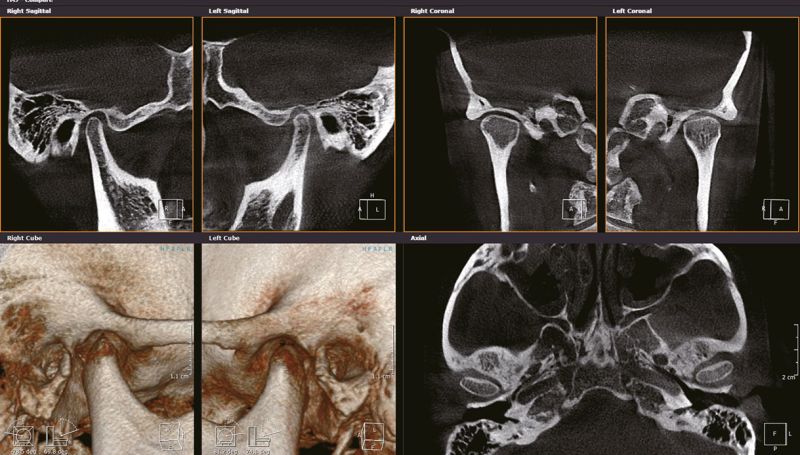

Диагностика височно-нижнечелюстных суставов (ВНЧС)

Конусно-лучевая компьютерная томография ВНЧС обеспечивает высокоточную визуализацию всех костных элементов сустава. Является информативным и достоверным методом диагностики при большинстве заболеваний сустава и смежных состояний.